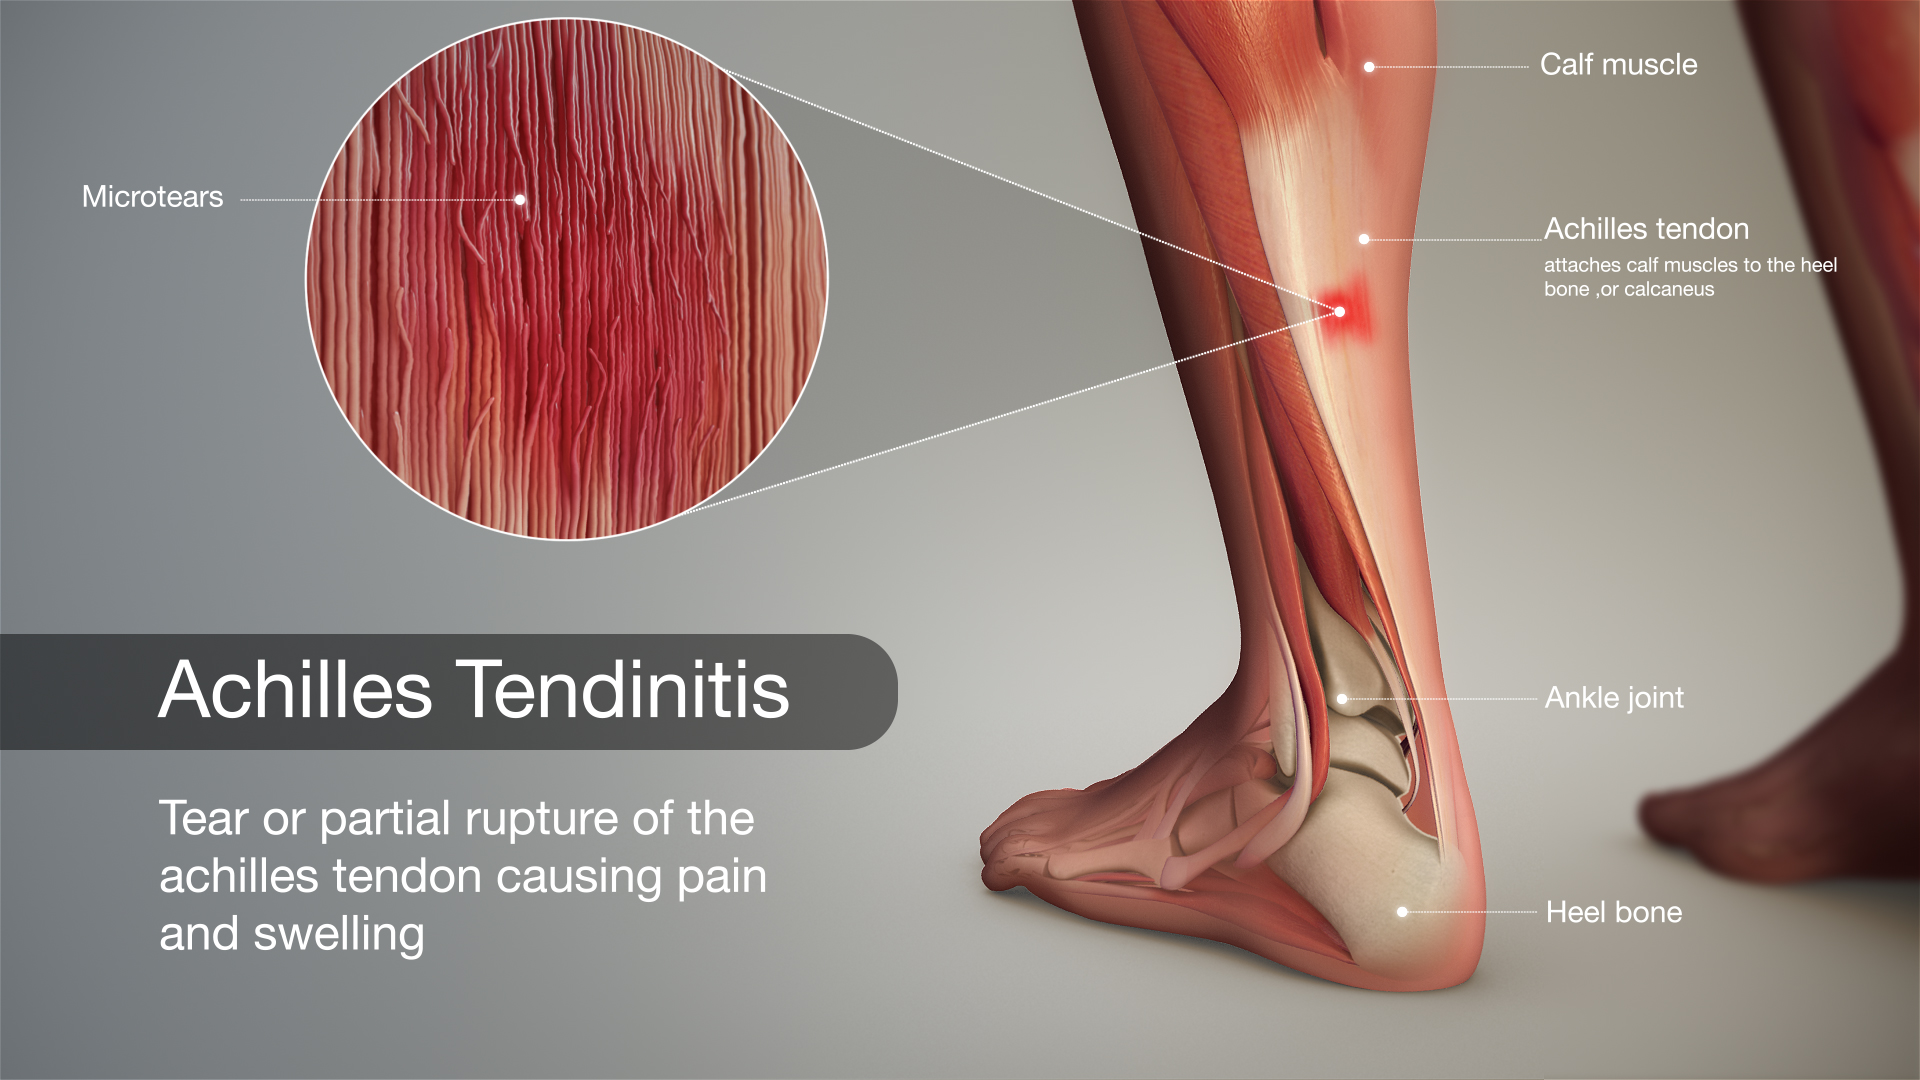

Тендинит Ахиллова сухожилия: симптомы и лечение

Раздел: Картинки на заметку